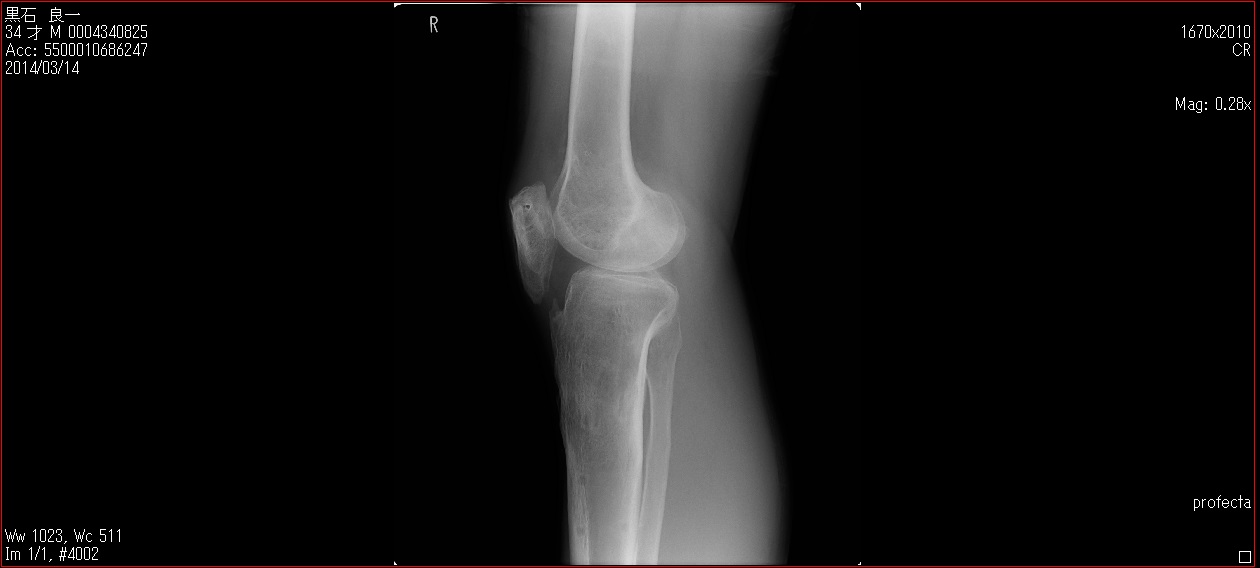

[Ortho] patella baja

Пациент 27 лет приехал для удлинения роста по эстетическим показаниям. Метод: крослатеральное двухэтапное удлинение голеней 4см и бедер 3 см.  Между этапами удлинения уезжал к себе домой в Японию на реабилитацию. Между этапами удлинения движения в коленных суставах разгибание полное сгибание 90-85. После выписки (февраль 2012) даны соответствующие указание постепенно возрастающей нагрузки и ЛФК коленных суставов.

В настоящий момент жалобы на ограничение сгибания в коленных суставах. Снимки прилагаются.

Вопрос: почему возникло такое осложнение? Поверьте приходилось удлинять намного больше, а тут всего на 3-4 см и такое осложнение на обеих конечностях у одного пациента?

Что можно сделать? У кого есть опыт лечения patella baja?